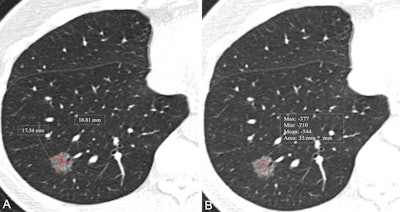

CT images show measurement of nodule size and mean CT attenuation in a 52-year-old woman. Transverse lung-window CT images were obtained without administration of contrast material. This lesion was pathologically proven to be an invasive adenocarcinoma. (A) Nodule size was measured by taking the mean of the maximum length and maximum width, defined as perpendicular to the length on the same axial image showing the maximum area of the nodule. The red lines indicate the length and width and measure 17.5 mm and 18.8 mm, respectively. (B) Nodule CT attenuation was measured by placing three regions of interest within the nodule covering two-thirds of the largest area while avoiding vessels and bronchioles. The red circle indicates CT attenuation and measures -544 HU.CT images show measurement of nodule size and mean CT attenuation in a 52-year-old woman. Transverse lung-window CT images were obtained without administration of contrast material. This lesion was pathologically proven to be an invasive adenocarcinoma. (A) Nodule size was measured by taking the mean of the maximum length and maximum width, defined as perpendicular to the length on the same axial image showing the maximum area of the nodule. The red lines indicate the length and width and measure 17.5 mm and 18.8 mm, respectively. (B) Nodule CT attenuation was measured by placing three regions of interest within the nodule covering two-thirds of the largest area while avoiding vessels and bronchioles. The red circle indicates CT attenuation and measures -544 HU.RSNA